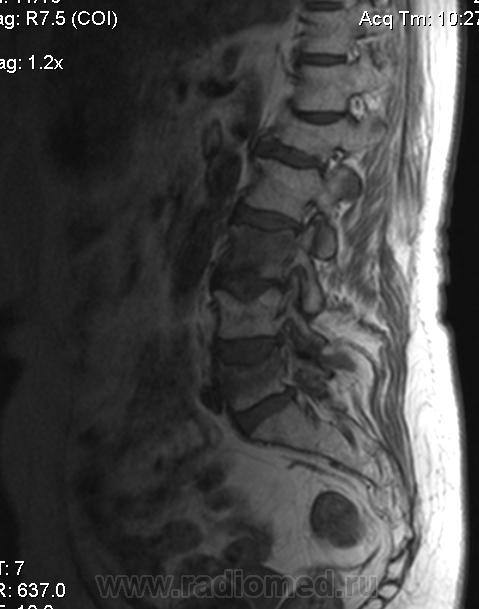

В анамнезе компрессионный перелом тела L1 позвонка в 1981г. На момент обследования компрессионные переломы тел L3, L5 позвонков, думаю остеопоротического характера. Непонятная зона в области боковой массы крестца на уровне S1-S3 слева (объемный процесс?)

Данных за объемный процесс в полости малого таза не вижу, матка удалена давно, шейка матки без особенностей, яичники бы посмотреть, буду рекомендовать УЗИ. Двояковогнутая деформация L3-L5 позвонков наблюдается при остеопорозе. Изменение интенсивности МР-сигнал от тел L3, L5 позвонков думаю, что за счет отека костного мозга в результате не так давно случившихся переломов на фоне остеопороза. Видно, что дуга, нижний суставной отросток L5 позвонка а аналогичными сигнальными характеристиками, вероятно тоже отек.  Непонятная зона в крестце- гемангиома? единичный крупный MTS?(что менее вероятно), изменения остеопоротического характера с возможной трещиной и отеком костного мозга? или еще что-то?

вижу старый перелом L1. ломаются L3,5 позвонки. с характерной для дисгормональной спондилопатии  вогнутостью площадок, отеком костного мозга. На секундарные изменения в крестце,  на мой взгляд, не похоже. А на Т2 как это выглядит?Ярко? Скорее это стрессовые    изменения  от недостаточности.